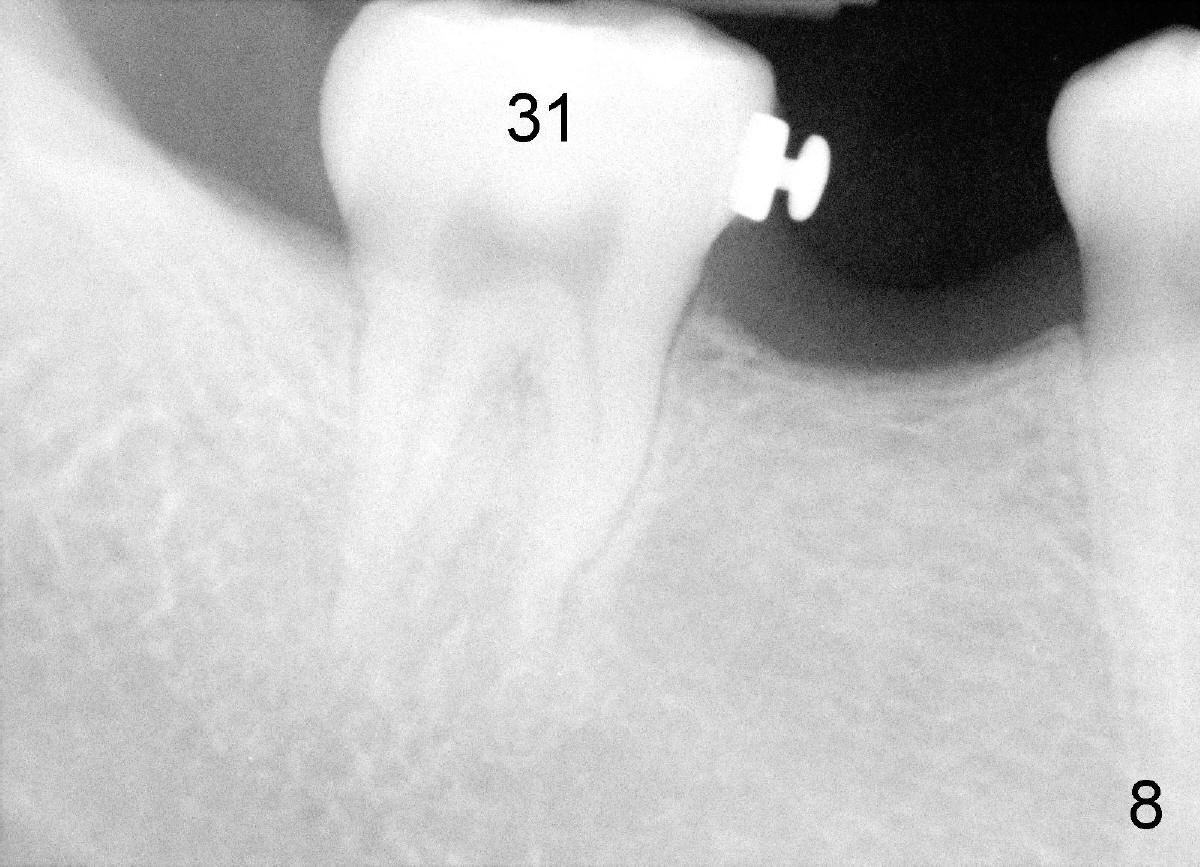

The tooth #31 is uprighted in six months (Fig.8, as compared to Fig.5). The edentulous space increases from 6 mm to 9 mm mesiodistally, which is still not enough. The M-D width of #19 is 12 mm. In fact, the tooth #2 has been intruded substantially (Fig.9. Compare to Fig.3). The possible reason for resistance of distal movement of #31 is an interference from the tooth #3 (Fig.10). A regular implant is placed intentionally in the distal aspect of the edentulous area (Fig.11: I). The next plan is to place temporary crown on the implant once it osteointegrates to raise the occlusion efficiently so that the tooth #31 is free to move distally with retraction of power chain attached to the mini-implant (as shown in Fig.2). The regular implant may be also used as anchorage to push #31 distally. See you later.